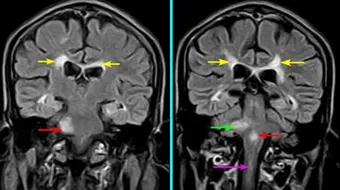

يحتوي العقل البشري من حوالي أربعة عشر مليون خلية عصبية، وعشرة أضعاف هذه الخلايا موجودة للتحكم بالأعصاب، وتنقسم هذه الخلايا إلى خلايا طرفية ومركزية، تتكون الخلايا المركزية من المخ، والدماغ الأوسط، والأجزاء من الدماغ التي تتحكم بحركة الجسم هي المخيخ، والعصب الدماغي، والنخاع الشوكي، والمخيخ هو الجزء الخلفي من الدماغ وهو أصغر من المخ ويعمل على تنفيذ الأوامر التي يتلقاها من المخ، ويساعد في حفظ التوازن، وضمور المخيخ هو مرض وراثي يصيب الدماغ ويؤثرعلى حركة الجسم وقد يقعد المريض عن الحركة، ويترافق مع أمراض عديدة مثل الشلل الرعاش والعديد من المشاكل التي تؤثر على قدرة المريض على أن يعيش حياة طبيعية.

- الجلطات ونقص تروية المخيخ.